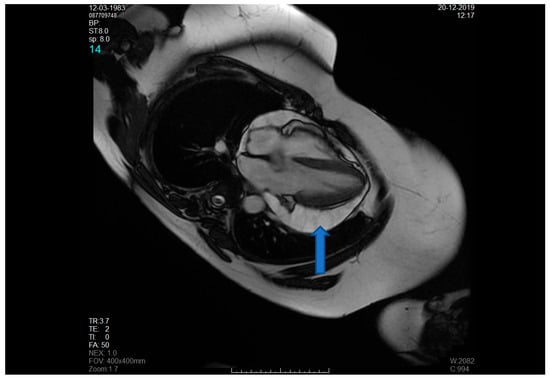

A Rare Case of Multilocular Mesothelial Inclusion Cysts of the Pericardium: Diagnosis, Treatment, Follow Up, with Comprehensive Review of the Literature

by Ali Shadmanian, Kosha Patel, Endre Alács, Henriette Gavallér, Szilva Agocs and Miklós Bitay

Background: Multilocular mesothelial inclusion cysts—also known as benign multicystic mesothelioma (BMM)—are rare, typically arising in the peritoneal cavity. Pericardial involvement is extremely uncommon and can pose diagnostic and therapeutic challenges due to their recurrent and infiltrative nature. Accurate diagnosis and surgical strategy are [...] Read more.

Background: Multilocular mesothelial inclusion cysts—also known as benign multicystic mesothelioma (BMM)—are rare, typically arising in the peritoneal cavity. Pericardial involvement is extremely uncommon and can pose diagnostic and therapeutic challenges due to their recurrent and infiltrative nature. Accurate diagnosis and surgical strategy are critical for management and recurrence prevention. Methods: We present the case of a 36-year-old woman with a prior history of malignant melanoma who developed recurrent multilocular cystic masses of the pericardium. Initial imaging with echocardiography, cardiac magnetic resonance (CMR), and computed tomography (CT) revealed multilocular pericardial cysts. Surgical resection was performed under cardiopulmonary bypass (CPB), but complete excision was limited due to epicardial infiltration. Histopathology confirmed a benign mesothelial origin. One year later, recurrence prompted a second surgical intervention with total pericardiectomy and Gore-Tex patch reconstruction. Results: Postoperative recovery was uneventful in both instances. Follow-up imaging at 6 and 12 months demonstrated no significant recurrence. Histological analysis confirmed benign cysts lined with mesothelial cells, positive for calretinin and WT-1. This represents one of the first documented living cases of pericardial BMM managed with staged surgery and total pericardiectomy. Conclusions: Pericardial BMM is a rare, benign, but potentially recurrent lesion. In cases of extensive or recurrent disease, total pericardiectomy may offer definitive treatment. Multimodal imaging, histopathological evaluation, and personalized surgical planning are essential for effective management. Full article

Figure 1